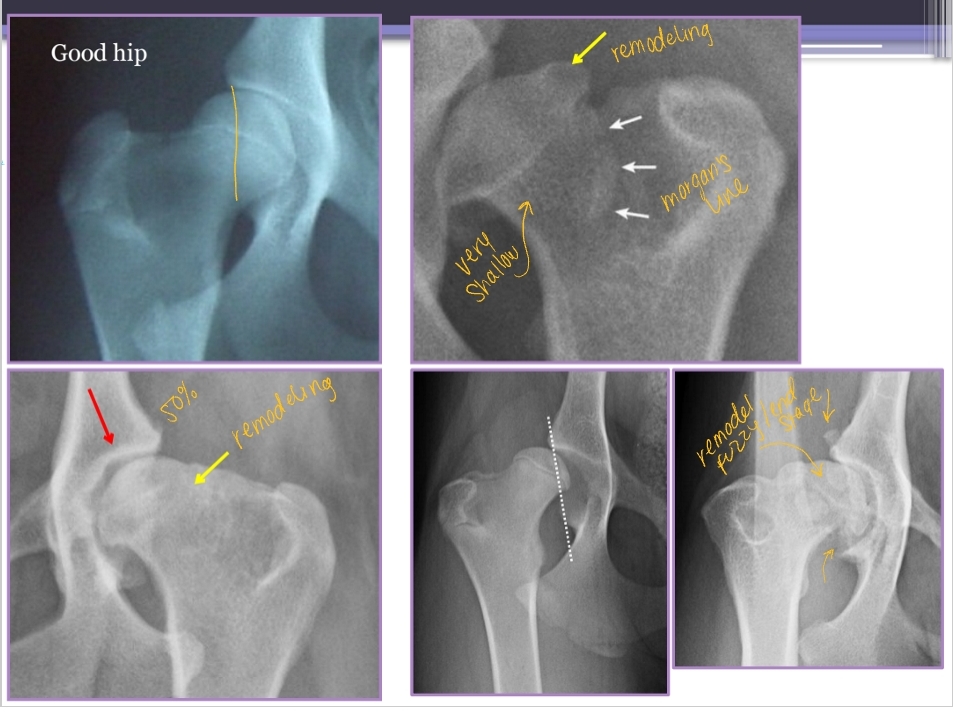

Diagnostic Imaging for Hip Dysplasia

VD most useful

Want >50% acetabular coverage!

Rads: Bone shape, remodeling, osteophytosis(neck), enthesiophytosis (Morgan’s line), laxity

Do not treat the radiograph!